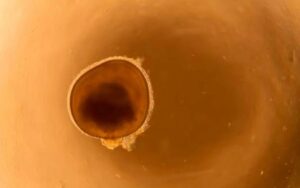

Glaucoma Cases Worldwide: Countries Most Affected

7:45 pm 21 Aug 2025